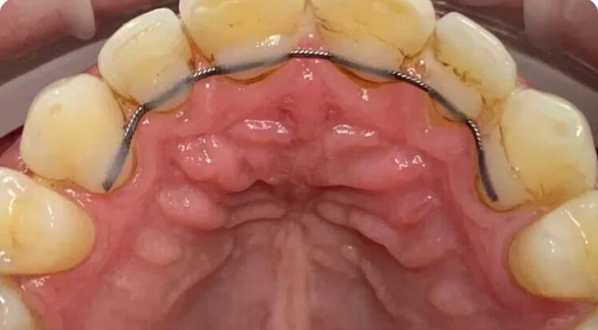

Профессиональная гигиена особенно важна при ортодонтическом лечении, ведь в повседневной жизни, дома, очень сложно поддерживать должный уровень гигиены полости рта! Даже если вы используете ирригатор и специальные ёршики! В нашей рубрике «до/после» вы видите то, что может быть с зубами при лечении брекетами, если не проводить своевременную чистку у врача-стоматолога. Марухно Дарья Александровна провела профессиональную чистку в несколько этапов, чтобы вернуть пациентке белизну ее собственных зубов! Брекет-система была поставлена не в нашей клинике, и почему пациентка не обратилась за профессиональной помощью раньше-вопрос) Но в данном случае, главное – итог! Кровоточивость после даже обычной чистки в такой клинической ситуации – естественный результат. Ведь обильный зубной налёт и зубной камень вызывают воспаление дёсен в виде гингивита, а порой даже пародонтита.

Доктор: Марухно Дарья Александровна